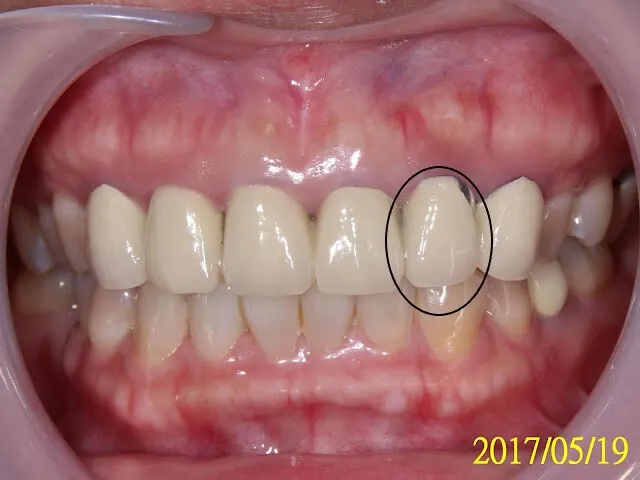

這位病人來的主訴(主要的訴求、想解決的問題),是想想換掉剛做2年的上前牙假牙。因為瓷裂,已補過多次。左上牙齦有時會壓痛,假牙內有時會塞東西,會臭臭的。目前在台灣這種假牙還是主流,金屬瓷牙(PFM),牆國用語是烤瓷牙。

原來連在一起的假牙,以修飾成人牙齦萎縮的問題,下詳內文另外也請注意6顆假牙邊緣的牙齦,全都有程度不一的暗紫紅色慢性發炎,尤其瓷裂處,看下圖拆完假牙的圖,才知造成發炎的真相,難怪病人說有時刷牙會流血

臨床我看,其實還好,病人上嘴唇在一般時候,是會蓋住瓷裂的地方,除非大笑之類的,旁人其實不會覺得那個假牙是有瑕疵的。我的意思是說,沒急迫性。但病人會故意拉開,堅持要處理,即使2年前才花幾萬塊做了這6顆假牙。